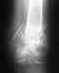

Re: Перелом лодыжки

В общем, бессимптомные фиксаторы можно не трогать, но это в общем. Зависит от того, где находятся спицы.